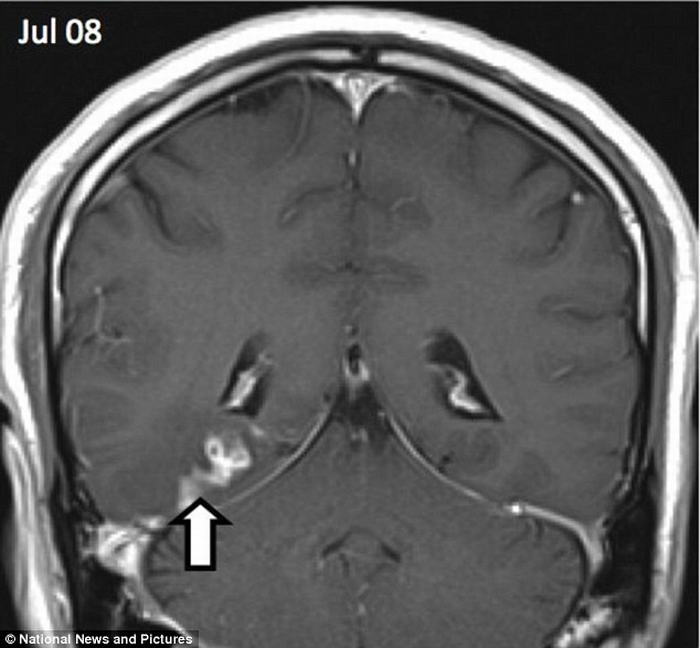

| Con sán đã ‘du lịch’ khoảng 5cm từ phía bên phải sang bên trái của não người đàn ông này trong suốt 4 năm. |